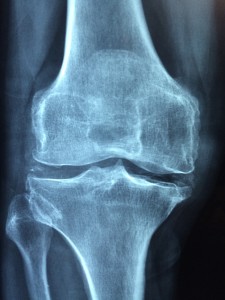

Kniegelenk: Ein Ersatz ist nicht immer ganz problemlos (Foto: pixabay.com, Taokinesis) |